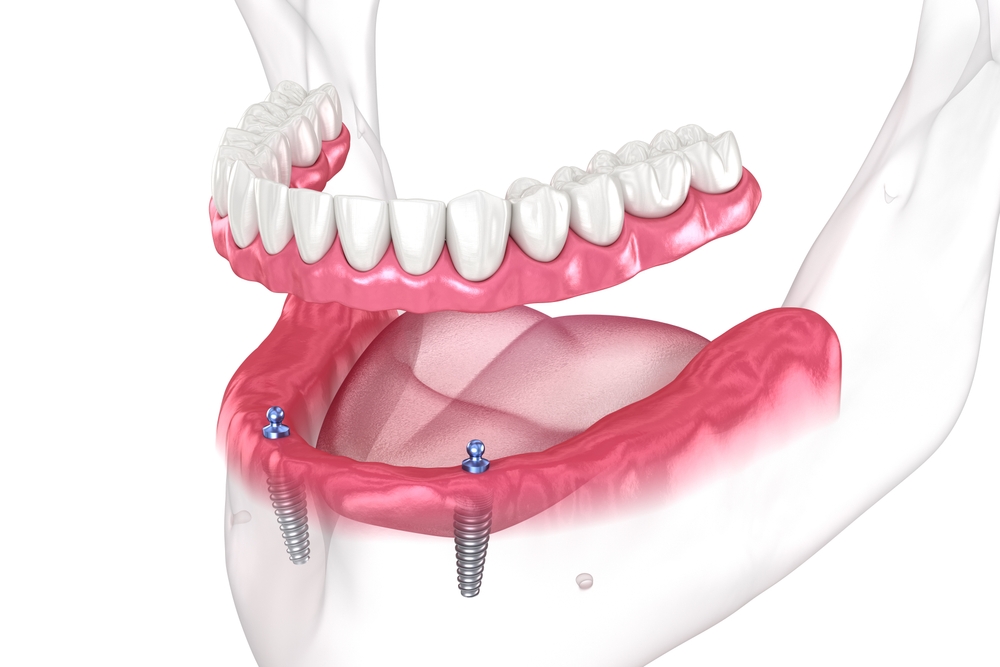

정기검진의 중요성

임플란트는 겉보기엔 멀쩡해 보여도,

내부에서는 나사가 풀리거나

잇몸뼈가 줄어드는 등 변화가

생길 수 있습니다.

따라서 임플란트 관리법중

빼놓을 수 없는 것이

바로 정기검진입니다.

일반적으로 6개월에서 1년에 한 번

정도는 검진을 받아 임플란트의

고정 상태, 보철물의 마모 여부,

잇몸 상태 등을 점검해야 합니다.

조기에 문제를 발견하면 간단히

조정이나 세정으로 해결할 수 있지만,

방치할 경우 더 큰 치료가

필요할 수 있습니다.